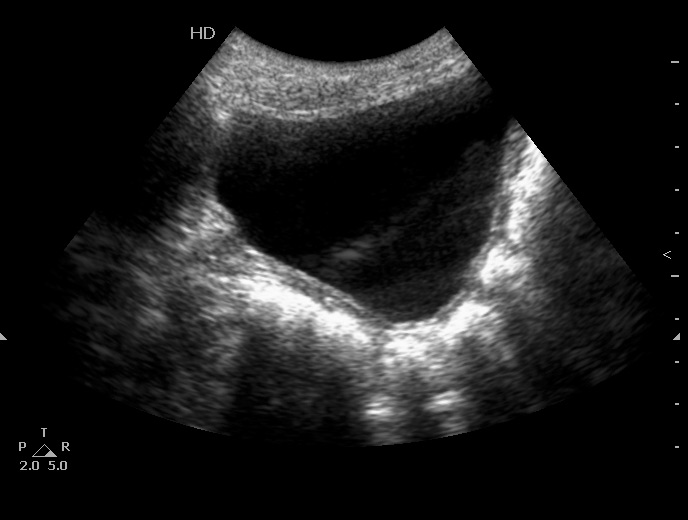

Мочевой пузырь:

Определяется небольшое расширение лоханок обеих почек, стенки их гиперэхогенные, утолщены.